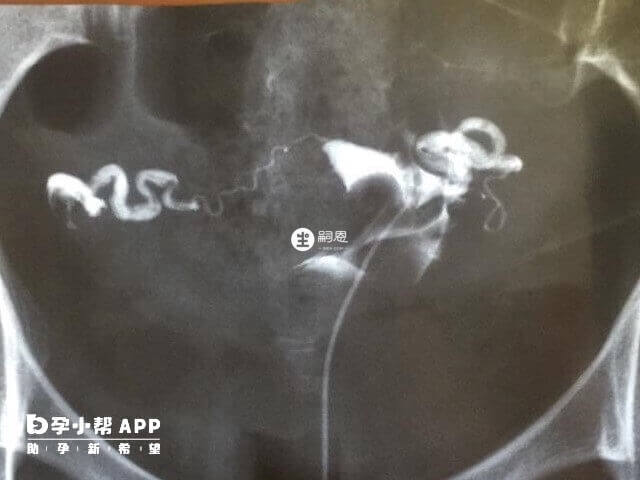

所謂的輸卵管積水其實就是在輸卵管炎以後,因粘連、閉鎖、黏膜細胞分泌積液存在管腔內,或因輸卵管炎症發生峽部及傘端粘連,阻塞後形成輸卵管積膿,管腔內膿細胞被吸收後最終成為水樣液體。

輸卵管積水對試管嬰兒的影響是比較大的,該液體會導致試管嬰兒移植以後或自然受孕不成功的現象發生,及時懷孕成功出現流產的概率也是非常大的,所以在試管移植前需要進行抽積水手術。以下就是關於輸卵管積水患者在試管移植前幾天進行抽積水手術好的相關分享:

7、試管移植前幾天抽輸卵管積水好